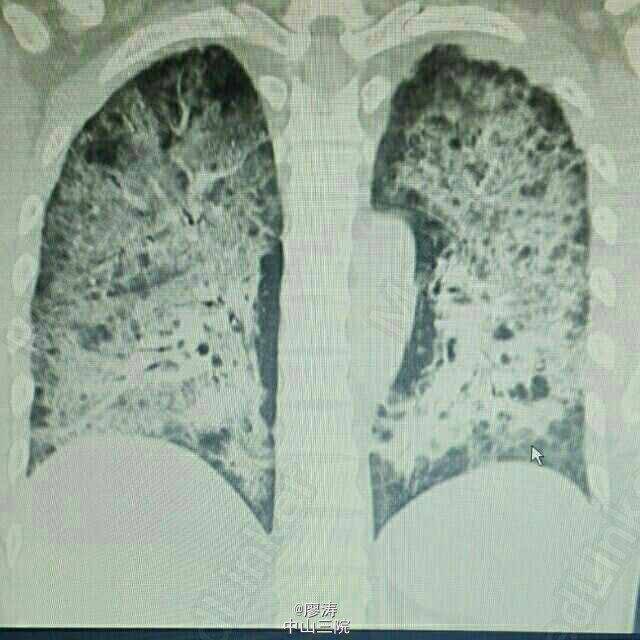

患者因“肾移植术后3月余,发热6小时入院”,患者2014-10-24在广西瑞康医院行同种异体肾移植术,术后肾功能恢复良好,肌酐控制在160umol/L左右,采用糖皮质激素+普乐可复+骁悉免疫抑制方案维持治疗,定期在肾移植专科门诊复查随诊,今日因寒战发热6h,体温38.3度入住我科。入院查体:T:37.6℃,P:92次/分,呼吸:20次/分,血压:109/67mmHg,无明显气促,入院前我院胸片提示:右下肺野炎症,肾功能稳定。入院后予拜复乐、米开民和更荷普欣联合抗感染治疗,治疗3天体温无明显好转。于1/2日改用舒普深、威凡和赛美维治疗,并停用口服免疫抑制剂,改为甲强龙40mg Bid维持,后病人体温逐渐降至正常,无诉胸闷气促,无咳嗽咳痰。因白细胞低,于3/2停用赛美维、予惠尔血升白细胞,继续使用舒普深和威凡抗感染,4/2复查CT提示双肺炎症较前吸收好转,双侧胸腔积液已吸收。后患者连续数日无发热,粒缺得到纠正,于9/2停用甲强龙,改回口服强的松+普乐可复+赛可平行免疫抑制治疗。10/2晚22:00患者再次发热,最高38.2度,伴有胸闷气促,予再次停用口服免疫抑制剂,改为甲强龙40mg Bid维持。11/2日患者气促加重,伴有胸闷不适,血气提示氧分压79.2mmHg,急查胸部CT提示双肺弥漫性炎症,较前明显加重,予加用百炎静、赛美维、日达仙,并加强对症支持治疗。请呼吸内科张扣兴教授会诊后转入综合ICU。转入后采用“美平+科赛斯+威凡+赛美维+百炎静+达菲”加强抗感染治疗,并停用口服抗排斥药物,改为小剂量MP维持。12/2上午患者气促加重,考虑重症肺炎并ARDS,予行气管插管接呼吸机辅助通气治疗,另予丙种球蛋白、日达仙、乌司他丁等加强对症支持治疗,同时护肝、护胃及维持水电解质平衡等器官功能支持治疗。患者症状缓解,16/2予拔除气管插管治疗。17/2复查胸部螺旋CT平扫提示:双肺炎症,考虑合并真菌感染可能;双肺上叶病灶较前吸收,余双肺病灶较前进展。予加用斯沃加强抗感染治疗。患者病情逐渐稳定好转,多日无发热,25/2日转回我科继续治疗。转回后患者一度再次出现WBC低下,予对症治疗后恢复,28/2,9/3日两次复查CT提示肺部感染持续好转吸收,综合呼吸科会诊意见后予逐步撤减抗生素,加回口服免疫抑制剂,采用FK506+MMF+Pred三联抗排斥治疗,继续维持口服威凡+SMZ抗感染治疗,复查FK506浓度9.8ng/ml,住院期间移植肾功能一直稳定,今日复查肌酐150umol/l,WBC 11.440x10E9/L,上级医师查房后指示给予办理出院,维持口服药物,门诊规律复查,并定期复查肺部CT,根据恢复情况决定抗感染疗程。 总结:肾移植术后患者服用免疫抑制剂,容易感染,对于此类患者在使用抗菌药物的同时应该适当调节免疫抑制剂的用法。重症肺炎有一个恢复的过程,像此类患者最后一次胸部CT检查提示还有炎症,但患者已经无明显不适,考虑为纤维化病变,需要一定的时间慢慢消散,不管怎样,我们救了这位患者。